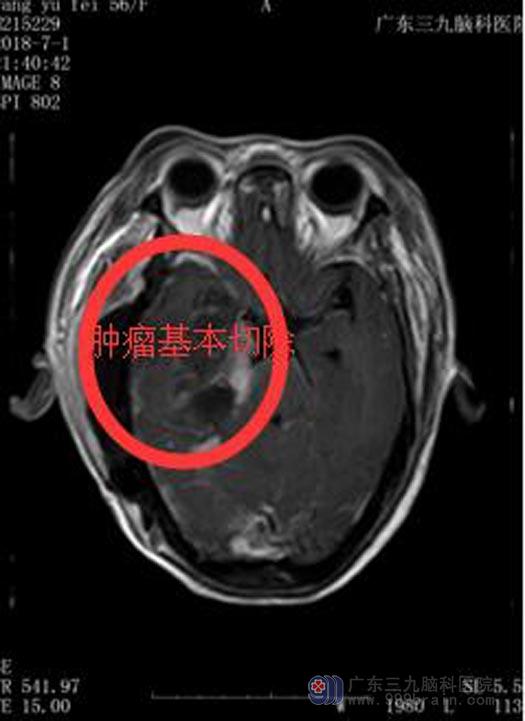

鲁副院长告诉他们,神经外科技术经过十多年的发展已今非昔比,脑膜瘤绝大多数属良性,只要术中能够切除干净,一般都不会复发,而且出现各种并发症、后遗症的几率很小。详细研究病情后决定行“右侧颅底、颞下窝肿瘤扩大切除+咽旁肿瘤切除+右侧下颌骨部分切除术”,王阿姨接受了这个方案。

完善相关手术准备后,由鲁明副院长主刀成功为她切除了肿瘤,手术过程顺利。术后王阿姨神志清楚,说话流利,生命体征平稳,四肢活动正常,恢复状况很好。